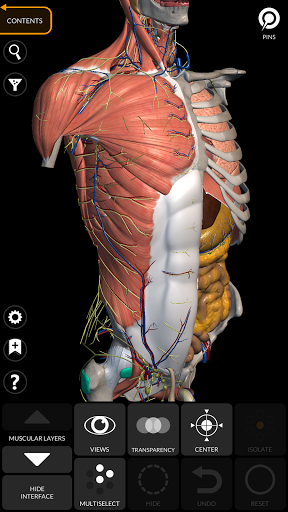

"Anatomy 3D Atlas" memungkinkan Anda mempelajari anatomi manusia dengan cara yang mudah dan interaktif.

Melalui antarmuka yang sederhana dan intuitif, Anda dapat mengamati setiap struktur anatomi dari sudut mana pun.

Model 3D anatomi sangat terperinci dan memiliki tekstur hingga resolusi 4k.

MODEL ANATOMI 3D

• Sistem muskuloskeletal

saraf • Sistem pernapasan • Sistem pencernaan • Sistem urogenital (pria dan wanita) • Sistem endokrin • Sistem limfatik • Sistem mata dan telinga FITUR • Antarmuka yang sederhana dan intuitif • Putar dan perbesar setiap model dalam ruang 3D • Opsi untuk menyembunyikan atau mengisolasi satu atau beberapa model yang dipilih • Filter untuk menyembunyikan atau menampilkan setiap sistem • Fungsi pencarian untuk menemukan setiap bagian anatomi dengan mudah • Fungsi penanda untuk menyimpan tampilan khusus • Rotasi cerdas yang menggerakkan pusat rotasi secara otomatis • Fungsi transparansi • Visualisasi otot melalui tingkat lapisan dari yang superfisial hingga yang terdalam • Dengan memilih model atau pin, istilah anatomi terkait akan muncul • Deskripsi otot: asal, • Tampilkan/ Sembunyikan antarmuka UI (sangat berguna dengan layar kecil) MULTIBAHASA • Istilah anatomi dan antarmuka pengguna tersedia dalam 11 bahasa: Latin, Inggris, Prancis, Jerman, Italia, Portugis, Turki, Rusia, Spanyol, Mandarin, Jepang, dan Korea • Istilah anatomi dapat ditampilkan dalam dua bahasa secara bersamaan PERSYARATAN SISTEM • Android 8.0 atau yang lebih baru, perangkat dengan RAM minimal 3GB Reversi